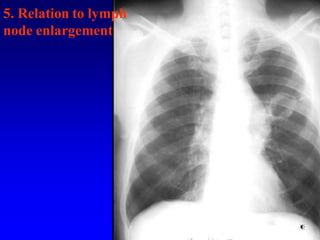

5. Relation to lymph

node enlargement